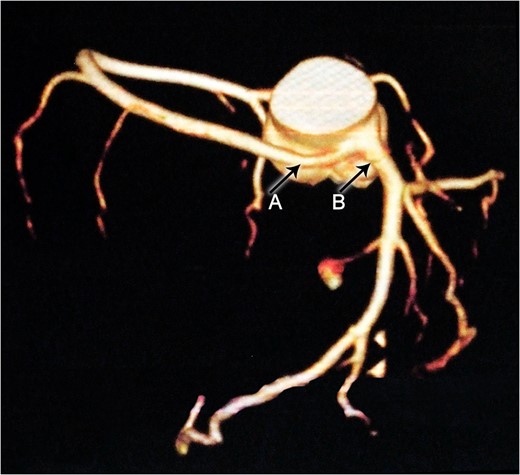

Axial CTA demonstrates an anomalous origin of RCA (Arrow A) which arises as a branch from LMCA (Arrow B).

Constructional CT demonstrates an anomalous origin of RCA (Arrow A) which arises as a branch from LMCA (Arrow B).